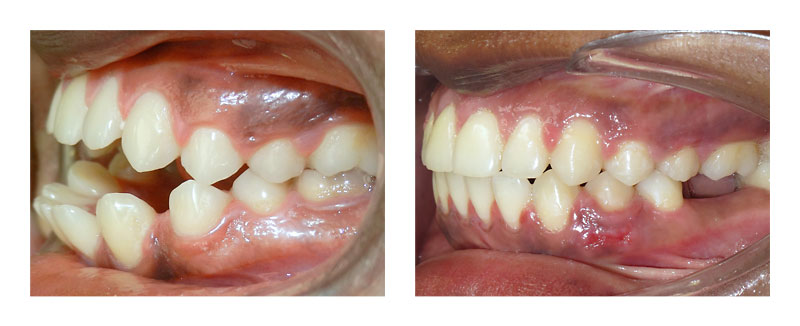

Cas Orthodontie Paris 7 : Recul d'incisives inférieures sur minivis

Le préjudice esthétique et fonctionnel lié à la position avancée des incisives inférieures (en avant des incisives supérieures) était très important. Ce trouble était d’origine fonctionnelle, car c’est la langue (basse et en avant) qui a poussé les incisives inférieures vers l’avant.

Du fait du bon emboîtement latéral des dents et de la présence d’espace à l’arcade inférieure, le traitement a consisté à reculer les incisives inférieures en prenant appui sur des minivis, dispensant de coopération, sans sollicitation des autres dents.

Le repositionnement des incisives inférieures a permis de retrouver une mastication efficiente au niveau de ces dents et de faire réapparaître les incisives supérieures dans le sourire. Le profil cutanée s’est amélioré sous l’effet du repositionnement de la lèvre inférieure. La préservation du résultat (obtenu en 2 ans) a imposé une contention et une rééducation de la langue.